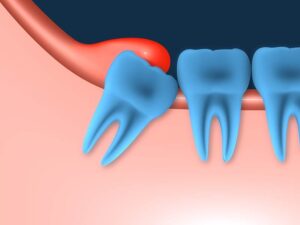

20 yaş dişlerinin gömülü kalma durumu çene veya dişin gelişimi ile ilgili olabilir. Diş arkasındaki yer darlığı ve dişeti, kemik veya komşu diş engeli dişin çıkabilmesine mani olabilir.

20 yaş dişleriyle ilgili bir diğer ağrı sebebi de yarı sürmüş 20 yaş dişetinin üzerinde dişeti cebi oluşur. Bu diş eti cebi, yediğimiz yemeklerin ve bakterilerin birikimi için müsait bir boşluk oluşturarak iltihaplanır ve şiddetli ağrılara sebep olur.